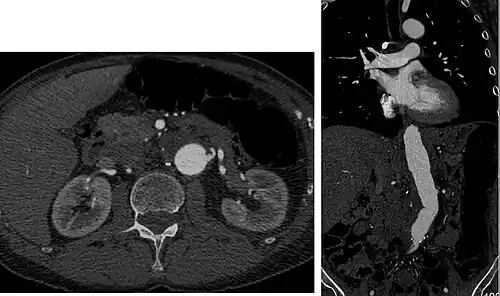

Detection and characterization of renal parenchymal masses is a frequent indication for CT. An initial noncontrast CT is important for detecting calcium or fat in a lesion, and to provide baseline attenuation of any renal masses. Following noncontrast scanning, intravenous contrast is injected and a corticomedullary phase is obtained at approximately 70 seconds (figure 7a, 7b). The corticomedullary phase is characterized by enhancement of the renal cortex as well as the renal vasculature. This phase is valuable in the evaluation of benign renal variants, lymphadenopathy and vasculature, however certain medullary renal masses may not be visible during this phase due to minimal enhancement of the medulla and collecting system. The parenchymal phase is obtained approximately 100–200 seconds after the injection of contrast material (figure 7c). Parenchymal phase imaging demonstrates continued enhancement of the cortex, enhancement of the medulla, and various levels of contrast material in the collecting system. The parenchymal phase is highly important for the detection and characterization of renal masses, parenchymal abnormalities, and the renal collecting system. This method of imaging does not evaluate for abnormalities of the collecting system.

Common renal masses can occasionally be differentiated from each other using this imaging technique. Renal cell carcinomas and oncocytomas typically demonstrate intense heterogeneous enhancement on the parenchymal phase images and cannot be reliably differentiated from each other but can be distinguished from other renal masses. Angiomyolipomas (AML's) also demonstrate intense contrast enhancement but characteristically contain macroscopic fat which can be detected on the noncontrast images, and can help to differentiate AML's from renal cell carcinomas and oncocytomas. Renal lymphoma on the other hand, will often have decreased enhancement when compared to the renal parenchyma on the parenchymal phase images.

![FIGURE 7. Selected images from a renal mass specific protocol CT. Corticomedullary phase (axial 7a) demonstrates peripheral enhancement of the renal cortex with minimal opacification of the renal medulla. There is a large renal cell carcinoma in the left kidney (right in image) which can be differentiated from the normal renal parenchyma by the heterogeneous and differential enhancement. The renal artery and vein are opacified in this phase as well. The collecting system is not opacified (coronal reformat 7b). In the parenchymal phase, the renal cortex and the medulla are enhancing. The renal cell carcinoma in the left kidney is not as well defined when compared to the corticomedullary phase images, but is actually slightly more conspicuous. There is some contrast noted within the collecting system during this phase (7c).[citation needed]](./_assets_/Corticomedullary_phase_CT_in_axial_and_coronal_plane%252C_and_parenchymal_phase%252C_of_renal_cell_carcinoma.jpg) FIGURE 7. Selected images from a renal mass specific protocol CT. Corticomedullary phase (axial 7a) demonstrates peripheral enhancement of the renal cortex with minimal opacification of the renal medulla. There is a large renal cell carcinoma in the left kidney (right in image) which can be differentiated from the normal renal parenchyma by the heterogeneous and differential enhancement. The renal artery and vein are opacified in this phase as well. The collecting system is not opacified (coronal reformat 7b). In the parenchymal phase, the renal cortex and the medulla are enhancing. The renal cell carcinoma in the left kidney is not as well defined when compared to the corticomedullary phase images, but is actually slightly more conspicuous. There is some contrast noted within the collecting system during this phase (7c).

FIGURE 7. Selected images from a renal mass specific protocol CT. Corticomedullary phase (axial 7a) demonstrates peripheral enhancement of the renal cortex with minimal opacification of the renal medulla. There is a large renal cell carcinoma in the left kidney (right in image) which can be differentiated from the normal renal parenchyma by the heterogeneous and differential enhancement. The renal artery and vein are opacified in this phase as well. The collecting system is not opacified (coronal reformat 7b). In the parenchymal phase, the renal cortex and the medulla are enhancing. The renal cell carcinoma in the left kidney is not as well defined when compared to the corticomedullary phase images, but is actually slightly more conspicuous. There is some contrast noted within the collecting system during this phase (7c).